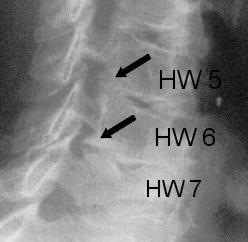

The operation gets performed by the use of general anaesthesia. The patient gets bedded lying on the belly whilst the head and the cervical spine get stretched. With the help of a surgical microscope the surgeon will carefully separate the thick muscles of the neck. During the entire operation the surgeon has the possibility to use an X-ray to ensure to be on the correct level. In the further procedure the surgeon cuts away the lateral parts of the vertebral arches which lowers the pressure on the nerve- root and releases the discomfort in most of the cases. This operation is also called Frykholm operation and commonly used due to the fact that the surgeon does not have to implant any artificial substances.